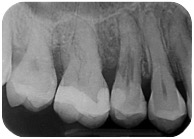

Dopo 5 anni la ragazza ha ancora un dente asintomatico e la rx indica che il processo si è arrestato.

Sconosciuto-X-20160414-124406-XJDGJ04C4J7B-4Sconosciuto-X-20160414-124407-XI+0ZQJHPJ47-4

Questo perché involontariamente avevo messo in atto una terapia corretta ad un problema che non conoscevo. Avevo rimosso nel miglior modo possibile fin dove potevo il tessuto di granulazione arrestando o rallentando il processo di distruzione del dente.